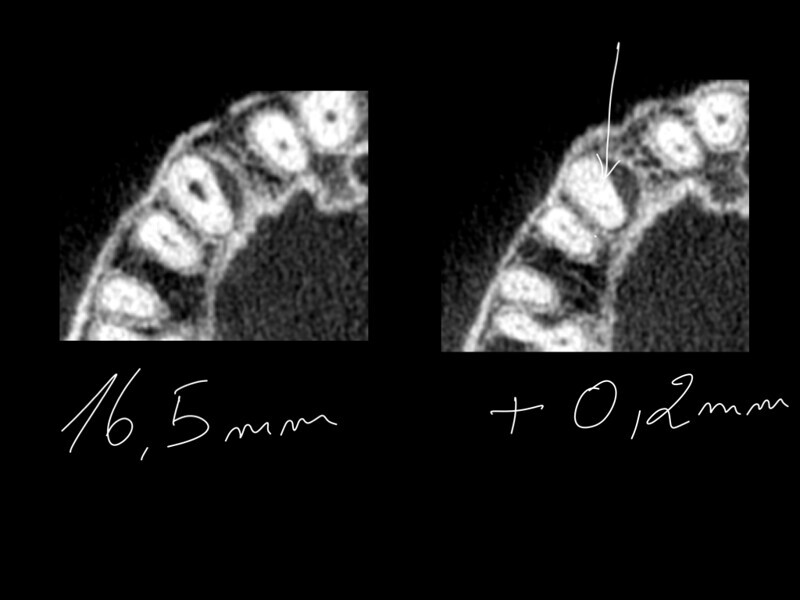

Treatment of the result of chronic activation of substance P